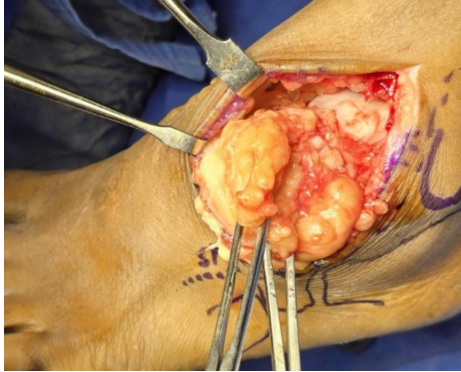

A calcaneonavicular coalition was identified, appearing as a fibro-osseous connection between the anterior process of the calcaneum and the lateral aspect of the navicular bone. Surgery was performed under spinal anesthesia with the patient in the supine position and a pneumatic tourniquet applied to the thigh. An anterolateral incision was made, centered over the swelling and extending from the lateral malleolus toward the sinus tarsi. The superficial peroneal nerve was identified early and carefully protected within the skin flap throughout the procedure. Dissection was carried out through the subcutaneous tissue and the deep fascia. The extensor digitorum brevis (EDB) muscle belly was encountered and divided to expose deeper structures. The inferior extensor retinaculum was incised longitudinally to improve visualization. A well-encapsulated, yellowish, lobulated mass was identified, adherent to the anterior capsule of the ankle joint but with no intra-articular extension. The capsule was preserved. The lesion, measuring almost 6 × 3 cm, was meticulously dissected off the capsule and adjacent tissues and excised en masse (Fig. 3 and 4).

Figure 3: Incision showing lipomatous tissue surrounding the ankle.

Figure 4: Lipoma size approximately 6 by 3 cm.

Intraoperatively, the anterior talofibular and anteroinferior tibiofibular ligament and talar cartilage were normal. Hemostasis was achieved with bipolar cautery. The mass was sent for histopathological examination, which confirmed a benign lipoma composed of mature adipose tissue (Fig. 5 and 6).